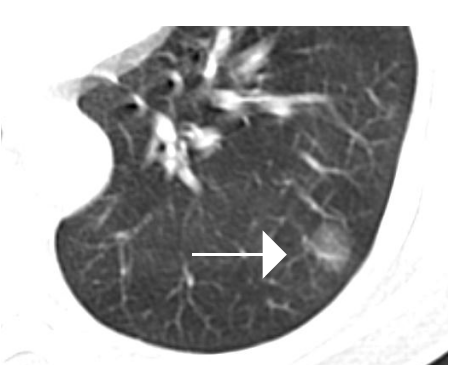

①前世:不典型腺瘤样增生(AAH),属于癌前病变,CT表现为纯磨玻璃结节,密度均匀,无肿瘤微血管。

②今生:原位腺癌(AIS),CT表现为部分实性磨玻璃结节,密度不均匀,磨玻璃背景中出现点状实性高密度影,出现肿瘤微血管。

③来世1:微浸润腺癌(MIA),CT表现为部分实性磨玻璃结节,密度不均匀,磨玻璃背景中出现点状实性高密度影,实性部分直径<5mm,较AIS密度增高,肿瘤微血管较AIS增粗、增多、边缘不规则,可出现胸膜凹陷征。

④来世2:浸润性腺癌(IAC),CT表现为部分实性磨玻璃结节,密度不均匀,磨玻璃背景中出现结节状实性高密度影,实性部分直径≥5mm,较MIA密度增高,肿瘤微血管较MIA增粗、增多、边缘不规则,出现胸膜凹陷征。

①如果是纯磨玻璃结节,考虑不典型腺瘤样增生(AAH),需要6—12个月CT随访复查,随访过程中出现“四增”就需要考虑手术了,“四增”包括增大、增密、增强和增粗。

②如果是部分实性磨玻璃结节,考虑原位腺癌(AIS),可以选择手术,如果各种原因暂时不能耐受手术者,可以6—9个月CT随访复查,随访过程中出现“四增”就需要考虑手术了。

③如果是部分实性磨玻璃结节,考虑微浸润腺癌(MIA)和浸润性腺癌(IAC)就需要考虑手术了。